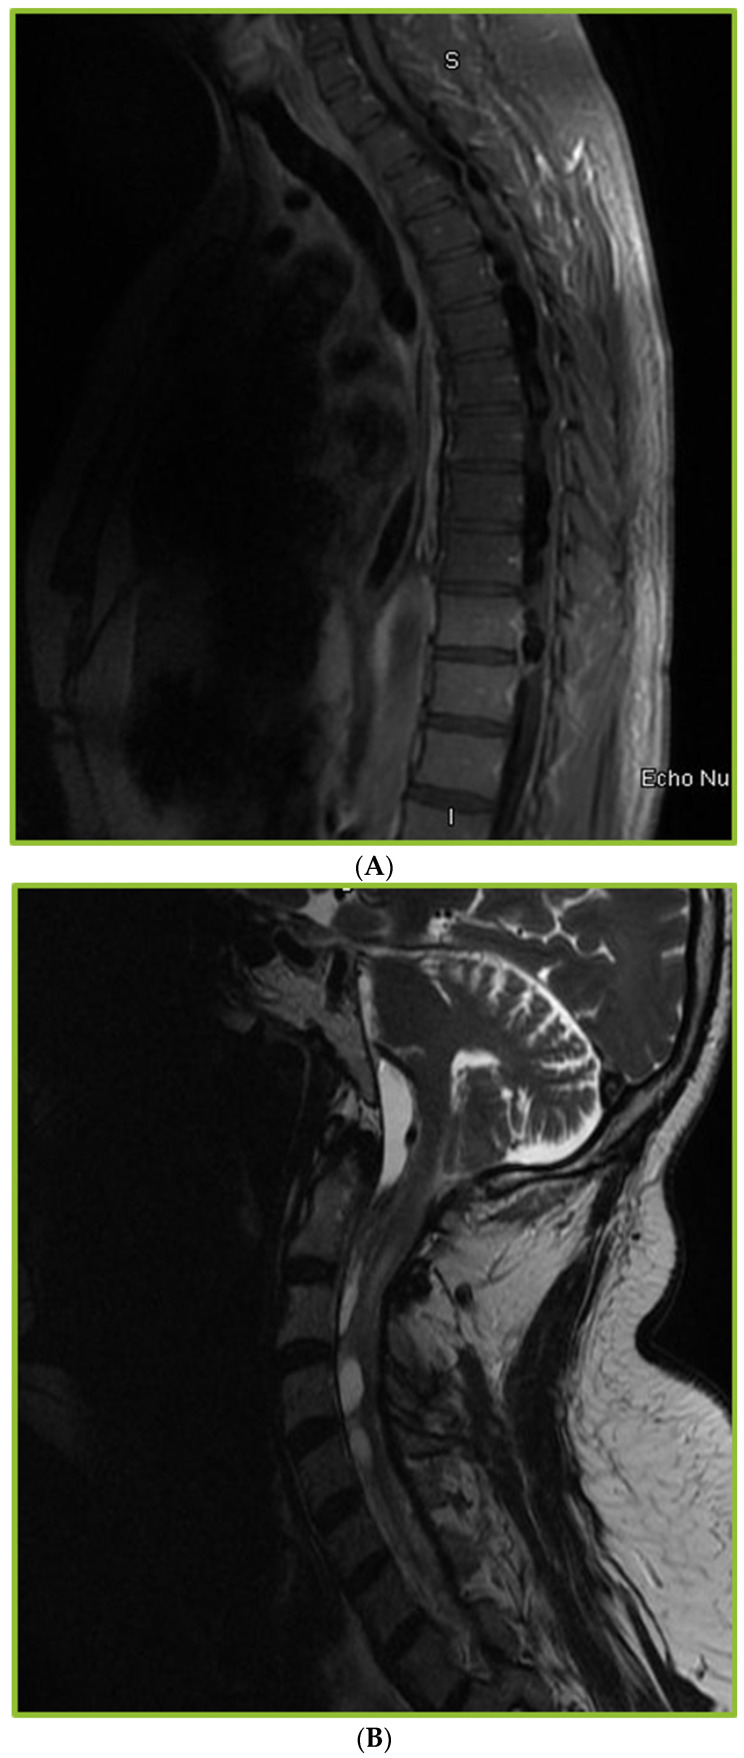

背景:球孢子菌性脑膜炎(CM)是最具侵袭性的球孢子菌病,需要终生抗真菌治疗,通常需要脑脊液(CSF)转移。长期CM可与脊髓并发症如蛛网膜炎相关。然而,描述CM患者蛛网膜炎的频率、临床和影像学特征的研究有限。方法:2010年1月至2020年12月,我们通过脑脊液培养、PCR或血清学鉴定了133例CM患者。其中,37例患者接受了脊柱成像。回顾了人口统计学、危险因素、症状、抗真菌治疗、手术治疗、随访、依从性、血清学趋势和影像学结果等方面的数据。结果:37例CM患者行脊柱影像学检查,其中30例出现异常。在我们的研究中,影像学异常包括轻脑膜增强(53%)、蛛网膜炎(53%)、脊髓空洞(23%)、脊髓信号异常(10%)和骨髓炎(7%)。在这30名患者中,90%的人有虚弱、麻木或尿潴留等症状。本研究中蛛网膜炎的发生率为12%。较高的初始脑脊液蛋白水平和颅内压与发生蛛网膜炎/脊髓空洞的高风险相关。CM的管理是具有挑战性的,分流失败(46%),药物不依从性(57%)和缺乏足够的随访(60%)。62%的患者存在持续性残疾。结论:CM患者可出现蛛网膜炎或脊髓空洞等脊柱并发症。由于在早期阶段缺乏症状,许多病例可能未被发现。CM管理的挑战,如分流失败,缺乏随访护理,药物不依从,是常见的。

Background: Coccidioidomycosis meningitis (CM) is the most aggressive form of coccidioidomycosis, requiring lifelong antifungal treatment and often cerebrospinal fluid (CSF) diversion. Long-standing CM can be associated with spinal complications such as arachnoiditis. However, studies describing the frequency, clinical, and imaging characteristics of arachnoiditis in patients with CM are limited. Methods: We identified 133 patients with CM based on CSF culture, PCR, or serology between January 2010 and December 2020. Of these, 37 patients underwent spinal imaging. Data on demographics, risk factors, symptoms, antifungal therapy, surgical management, follow-up visits, adherence, serological trends, and imaging findings were reviewed. Results: Abnormal findings were observed in 30 of the 37 patients with CM who underwent spinal imaging. The imaging abnormalities noted in our study included leptomeningeal enhancement (53%), arachnoiditis (53%), syringomyelia (23%), cord signal abnormalities (10%), and osteomyelitis (7%). Of the 30 patients, 90% had symptoms, such as weakness, numbness, or urinary retention. The incidence of arachnoiditis in the present study was 12%. Higher initial CSF protein levels and intra cranial pressure were associated with a higher risk of developing arachnoiditis/syringomyelia. Management of CM was challenging, as evidenced by shunt failure (46%), medication non-compliance (57%), and lack of adequate follow-up (60%). Persistent disabilities were noted in 62% of the patients. Conclusions: Patients with CM develop spinal complications such as arachnoiditis, or syringomyelia. Many cases may go undetected due to lack of symptoms in early stages. CM management challenges such as shunt failure, lack of follow-up care, and medication noncompliance, were frequent.